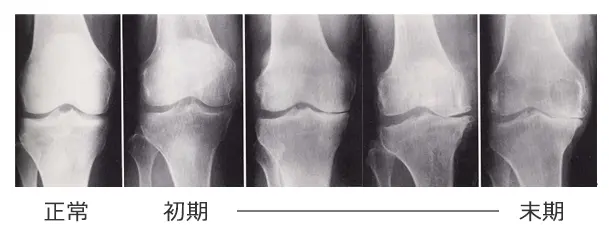

変形性関節症は関節の軟骨がすり減り変形・痛みを引き起こす病気で、QOL(生活の質)や健康寿命を低下させる大きな一因となっています。

変形性膝関節症

日本国内の変形性膝関節症患者の数は自覚症状のある方が約1,000万人、自覚症状のない方も含めると約3,000万人で、男女比は1:4です。明らかな原因はわかっていませんが、加齢、肥満、体型、筋力、職業、遺伝などが関係すると考えられています。